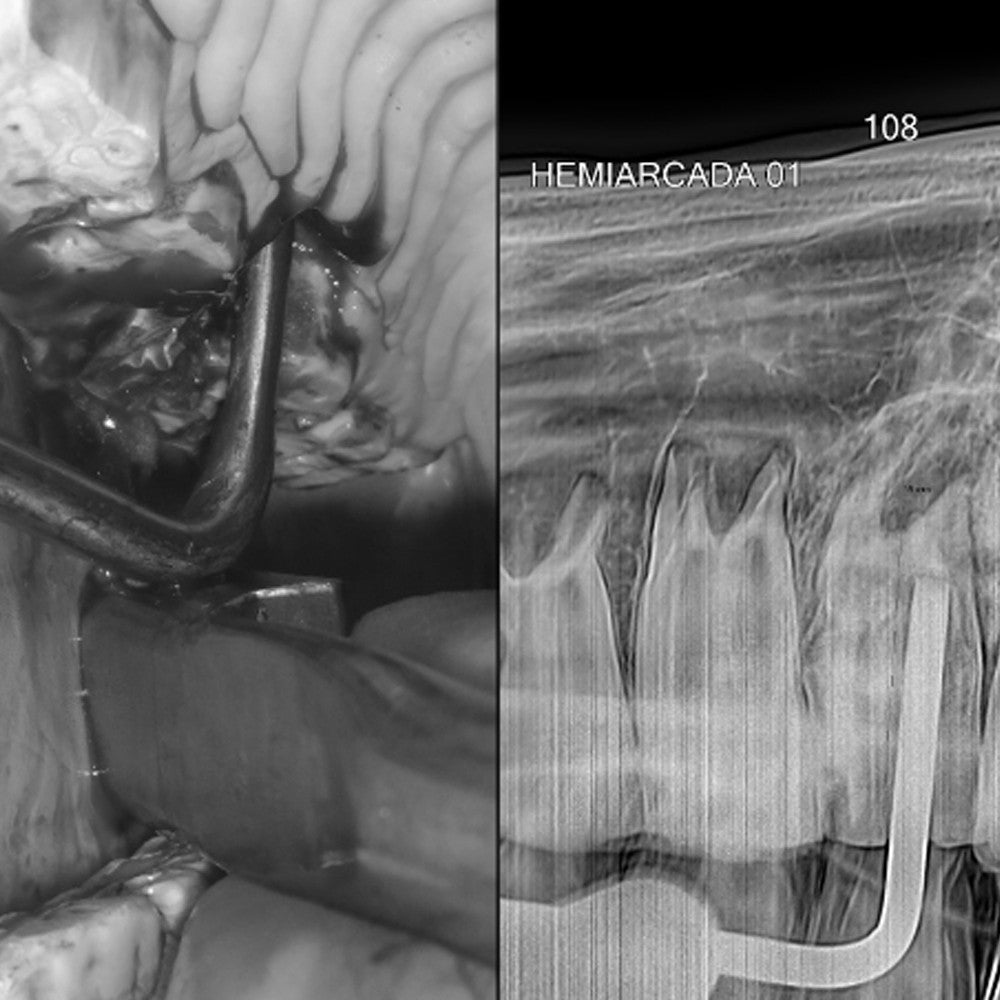

Syndesmotomes are specialized dental instruments designed to assist in intraoral dental extractions by severing the periodontal ligaments that connect the tooth to the alveolar bone.

The set of elevators includes eight pieces, each with varying shapes, lengths, and widths. These elevators are used following the application of periotomes.

The design and sharpening of the elevators allow for effective movement to detach the gum tissue and insert the instruments between the tooth and the alveolus. This process facilitates the rupture of the periodontal ligaments, dislocation, and tooth movement.